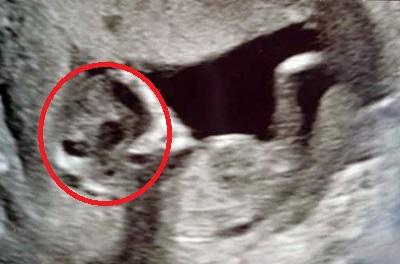

O femeie însărcinată a mers la un control de rutină și a făcut o ecografie ca să se asigure că bebelușul ei este bine, doar că a trăit un adevărat șoc atunci când a văzut ce a apărut pe monitor!

Femeia a trăit însă un adevărat șoc atunci când a privit monitorul aparatului ecograf, căci în imagine a apărut un element ce i-a dat fiori în adevăratul sens al cuvântului!

Mai exact, chiar lângă silueta copilului, Sophie a văzut un chip terifiant ce semăna izbitor de mult cu cel al unui extraterestru!

Medicii au analizat atent situația și au liniștit-o pe tânăra mămică, spunându-i că sarcina decurge cum trebuie și că nu are motive de îngrijorare, imaginea stranie fiind, cel mai probabil, o iluzie optică cauzată de aparatul ecograf, la reproducerea diferitelor densități și materii din uter.

Totuși, Sophie a pus poza pe internet și imaginea a devenit imediat virală în toată lumea, stârnind un val de reacții diverse în mediul online. Unii au fost de părere că este un semn de rău augur, alții s-au amuzat de modul „prăpăstios” al mamei de-a privi lucrurile!